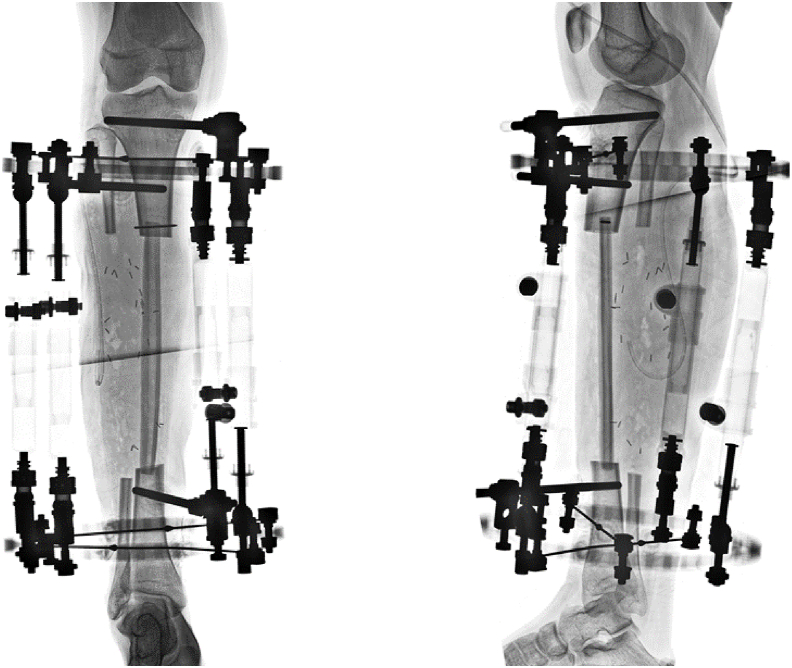

A 12+9-year-old female-assigned at birth diagnosed with osteofibrous dysplasia of her right tibia underwent 15cm bone resection, ipsilateral pedicled fibular graft, and frame application without a thorough multidisciplinary preoperative evaluation. During her course of treatment, the patient's mood and ability to participate in her own care (e.g. showering, feeding herself on a regular and consistent basis, completing home exercises) declined precipitously, and she began to endorse symptoms of suicidal ideation and non-suicidal self-injury behavior. Eventually the patient had to be admitted to the team's pediatric orthopaedic institution and was later transferred to an intensive outpatient mental health program for safety and mood stabilization. Due to multiple absences, the patient was prematurely dismissed from the mental health program and subsequently refused to participate with any sort of mental health intervention. Simultaneously, she struggled to cope with the demands of her external fixation treatment.Broadly, this case highlights the critical importance of thorough psychological assessment prior to consideration of limb lengthening and/or reconstruction. Psychological assessment should first establish the patient's baseline mental health, identify any extant mental health symptoms, and connect the patient with appropriate intervention as needed. Second, psychological assessment should establish the family's baseline functioning, including caregiver availability and support as well as emotional and logistical resources available to support treatment. Third, psychological assessment should continue throughout the course of treatment, in order to identify real time possible changes in a patient's mental health and intervention needs.

一名12+9岁女性,出生时被诊断为右胫骨骨纤维性发育不良,在没有进行全面的多学科术前评估的情况下,接受了15cm骨切除、同侧带蒂腓骨移植和框架应用。在治疗过程中,患者的情绪和参与自我护理的能力(如洗澡、定期和持续地自己进食、完成家庭运动)急剧下降,并开始出现自杀意念和非自杀自残行为的症状。最终,患者不得不住进该团队的儿科骨科机构,随后被转移到一个强化的门诊心理健康项目,以确保安全和情绪稳定。由于多次缺席,患者被过早地从心理健康项目中解雇,随后拒绝参加任何形式的心理健康干预。同时,她也在努力应对外固定治疗的要求。总的来说,这个病例强调了在考虑肢体延长和/或重建之前进行彻底的心理评估的重要性。心理评估应首先确定患者的心理健康基线,确定任何现存的心理健康症状,并根据需要将患者与适当的干预联系起来。第二,心理评估应该建立家庭的基本功能,包括照顾者的可用性和支持,以及支持治疗的情感和后勤资源。第三,心理评估应在整个治疗过程中持续进行,以便实时识别患者心理健康和干预需求的可能变化。关键概念:(2)术前心理评估应建立患者的基线心理健康状况,并确定任何先前存在的心理健康问题。(3)术前心理评估应建立患者的家庭基线功能,重点关注认知、(4)心理评估应在整个治疗过程中持续进行,以便及时识别治疗过程中出现的任何情绪问题。